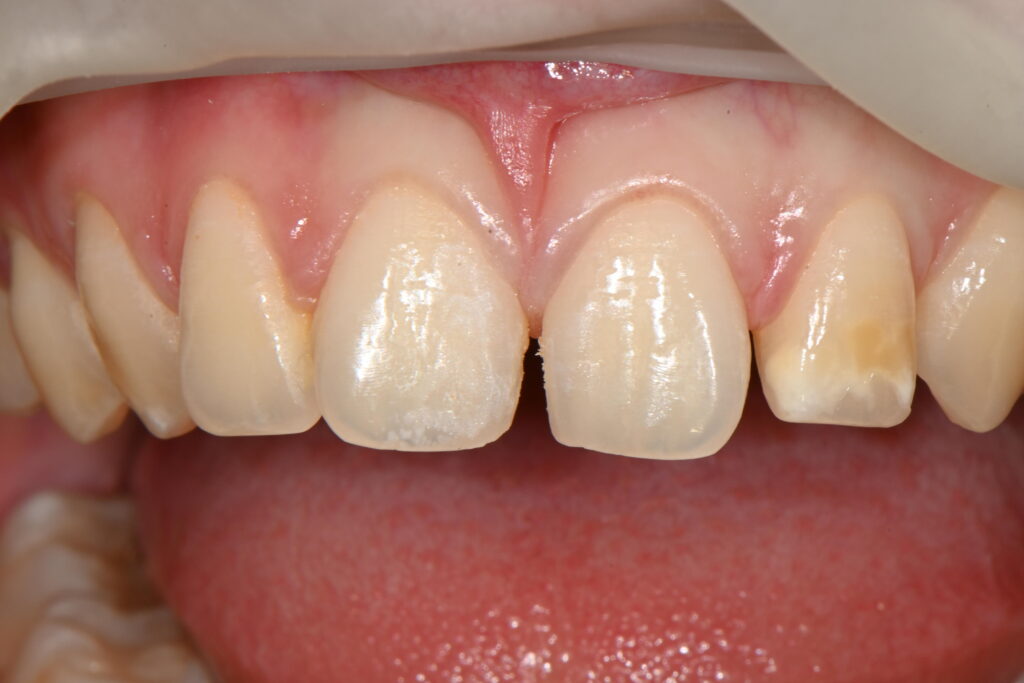

전체적인 앞니 미소가 힘들다고 내원하신경우입니다

이렇게 앞니가 벌어진 경우는 원인이 참 많습니다

이 케이스경우에는 치아형태의 이상입니다

일명 외소치와 쐐기모양 치아형태를 동시에 나타나고 있습니다

쐐기모양의 치아형태 모양을 띄면서 사이공간이 생긴 케이스입니다